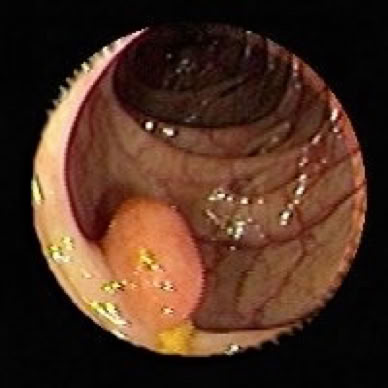

Darmpolyp

• Darmpolypen (meist gutartige Wucherungen)

• Bösartige Darmerkrankungen (Darmkrebs, der oft aus Polypen entsteht)